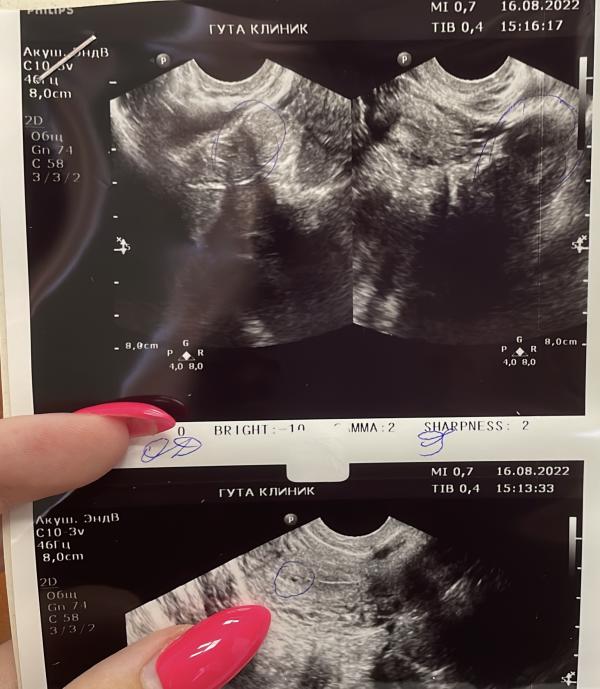

После отмены КОК в мае был нерегулярный цикл, то 35 дней, то 21 день. Последние месячные были 8 июля, но когда была овуляция я не знаю. Делала тест обычный 9 августа, он показал одну полоску , 11 августа сдала хгч он был 57. Вчера (16 августа) сходила к гинекологу , она сделала узи и сказала , что либо это плодное яйцо (1.3 мм) на узи внизу, где палец , либо реакция эндометрия на беременность. Сказала сдать хгч в динамике и прийти к ней через неделю на узи,. Вчера сдала хгч, результат 1122.

Плодное яйцо появляется на УЗИ при хгч от 1000, так что, я бы решила, что это беременность и пя на УЗИ.